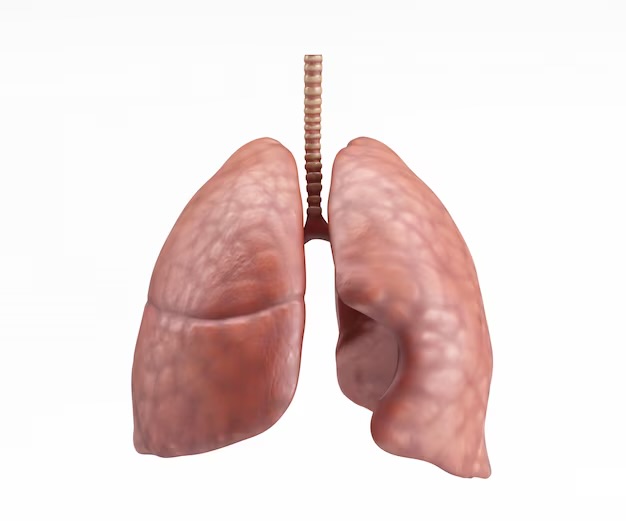

El color rosado claro del pulmón normal se debe a su rica vascularización y su estructura microscópica. En los niños, cuyos pulmones están en pleno desarrollo y función, este color es especialmente prominente debido a la alta densidad de pequeños vasos sanguíneos que irrigan el tejido pulmonar. Además, la superficie interna de los alvéolos, donde ocurre el intercambio de gases, está revestida de capilares sanguíneos, lo que contribuye al tono rosado característico.

Las pequeñas figuras poligonales que se dibujan en la superficie del pulmón corresponden a los contornos de los lobulillos pulmonares, que son las unidades estructurales y funcionales básicas del órgano. Cada lobulillo pulmonar está delimitado por tabiques de tejido conectivo que contienen bronquiolos, vasos sanguíneos y tejido pulmonar. Con la acumulación de polvo en la trama conectiva, estos tabiques se hacen más visibles, delineando los límites de los lobulillos y creando las figuras poligonales características.